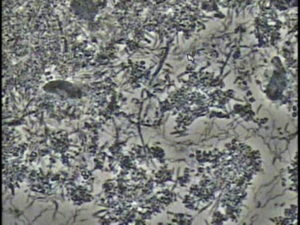

【衝撃の事実】「虫歯」=ばい菌だと思っていませんか?

香川県高松市の咬み合わせ専門歯科医院 吉本歯科医院の吉本彰夫です。 「毎日歯磨きをしているのに、なぜか虫歯になる」 「甘いものを控えているのに、歯に穴があいてしまった」もしあなたがそう感じているなら、それはあなたの「虫歯 […]

歯磨きしているのに虫歯が再発する理由

香川県高松市の噛み合わせ専門歯科医院 吉本歯科医院の吉本彰夫です。 どうして虫歯になるのか?虫歯になる原因は何か? 多くの方が 「バイ菌」だ、 とお答になります。 だから「歯磨きさえしていれば大丈夫」と思っていらっしゃい […]

従来型の虫歯治療では再発を起こすのは当然です。

香川県高松市の咬み合わせ専門の吉本歯科医院、吉本彰夫です。 皆さんは今まで虫歯になった時、どんな治療を受けてこられましたか? 多くの方が受けられた治療は「虫歯部分を大きく削りとり被せ物でふたをする」という一般的な治療だと […]